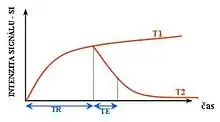

T1 and T2

Each tissue returns to its equilibrium state after excitation by the independent relaxation processes of T1 (spin-lattice; that is, magnetization in the same direction as the static magnetic field) and T2 (spin-spin; transverse to the static magnetic field). To create a T1-weighted image, magnetization is allowed to recover before measuring the MR signal by changing the repetition time (TR). This image weighting is useful for assessing the cerebral cortex, identifying fatty tissue, characterizing focal liver lesions, and in general, obtaining morphological information, as well as for post-contrast imaging. To create a T2-weighted image, magnetization is allowed to decay before measuring the MR signal by changing the echo time (TE). This image weighting is useful for detecting edema and inflammation, revealing white matter lesions, and assessing zonal anatomy in the prostate and uterus.

The information from MRI scans comes in the form of image contrasts based on differences in the rate of relaxation of nuclear spins following their perturbation by an oscillating magnetic field (in the form of radiofrequency pulses through the sample).[18] The relaxation rates are a measure of the time it takes for a signal to decay back to an equilibrium state from either the longitudinal or transverse plane.

Magnetization builds up along the z-axis in the presence of a magnetic field, B0, such that the magnetic dipoles in the sample will, on average, align with the z-axis summing to a total magnetization Mz. This magnetization along z is defined as the equilibrium magnetization; magnetization is defined as the sum of all magnetic dipoles in a sample. Following the equilibrium magnetization, a 90° radiofrequency (RF) pulse flips the direction of the magnetization vector in the xy-plane, and is then switched off. The initial magnetic field B0, however, is still applied. Thus, the spin magnetization vector will slowly return from the xy-plane back to the equilibrium state. The time it takes for the magnetization vector to return to its equilibrium value, Mz, is referred to as the longitudinal relaxation time, T1.[19] Subsequently, the rate at which this happens is simply the reciprocal of the relaxation time: . Similarly, the time in which it takes for Mxy to return to zero is T2, with the rate .[20] Magnetization as a function of time is defined by the Bloch equations.

T1 and T2 values are dependent on the chemical environment of the sample; hence their utility in MRI. Soft tissue and muscle tissue relax at different rates, yielding the image contrast in a typical scan.